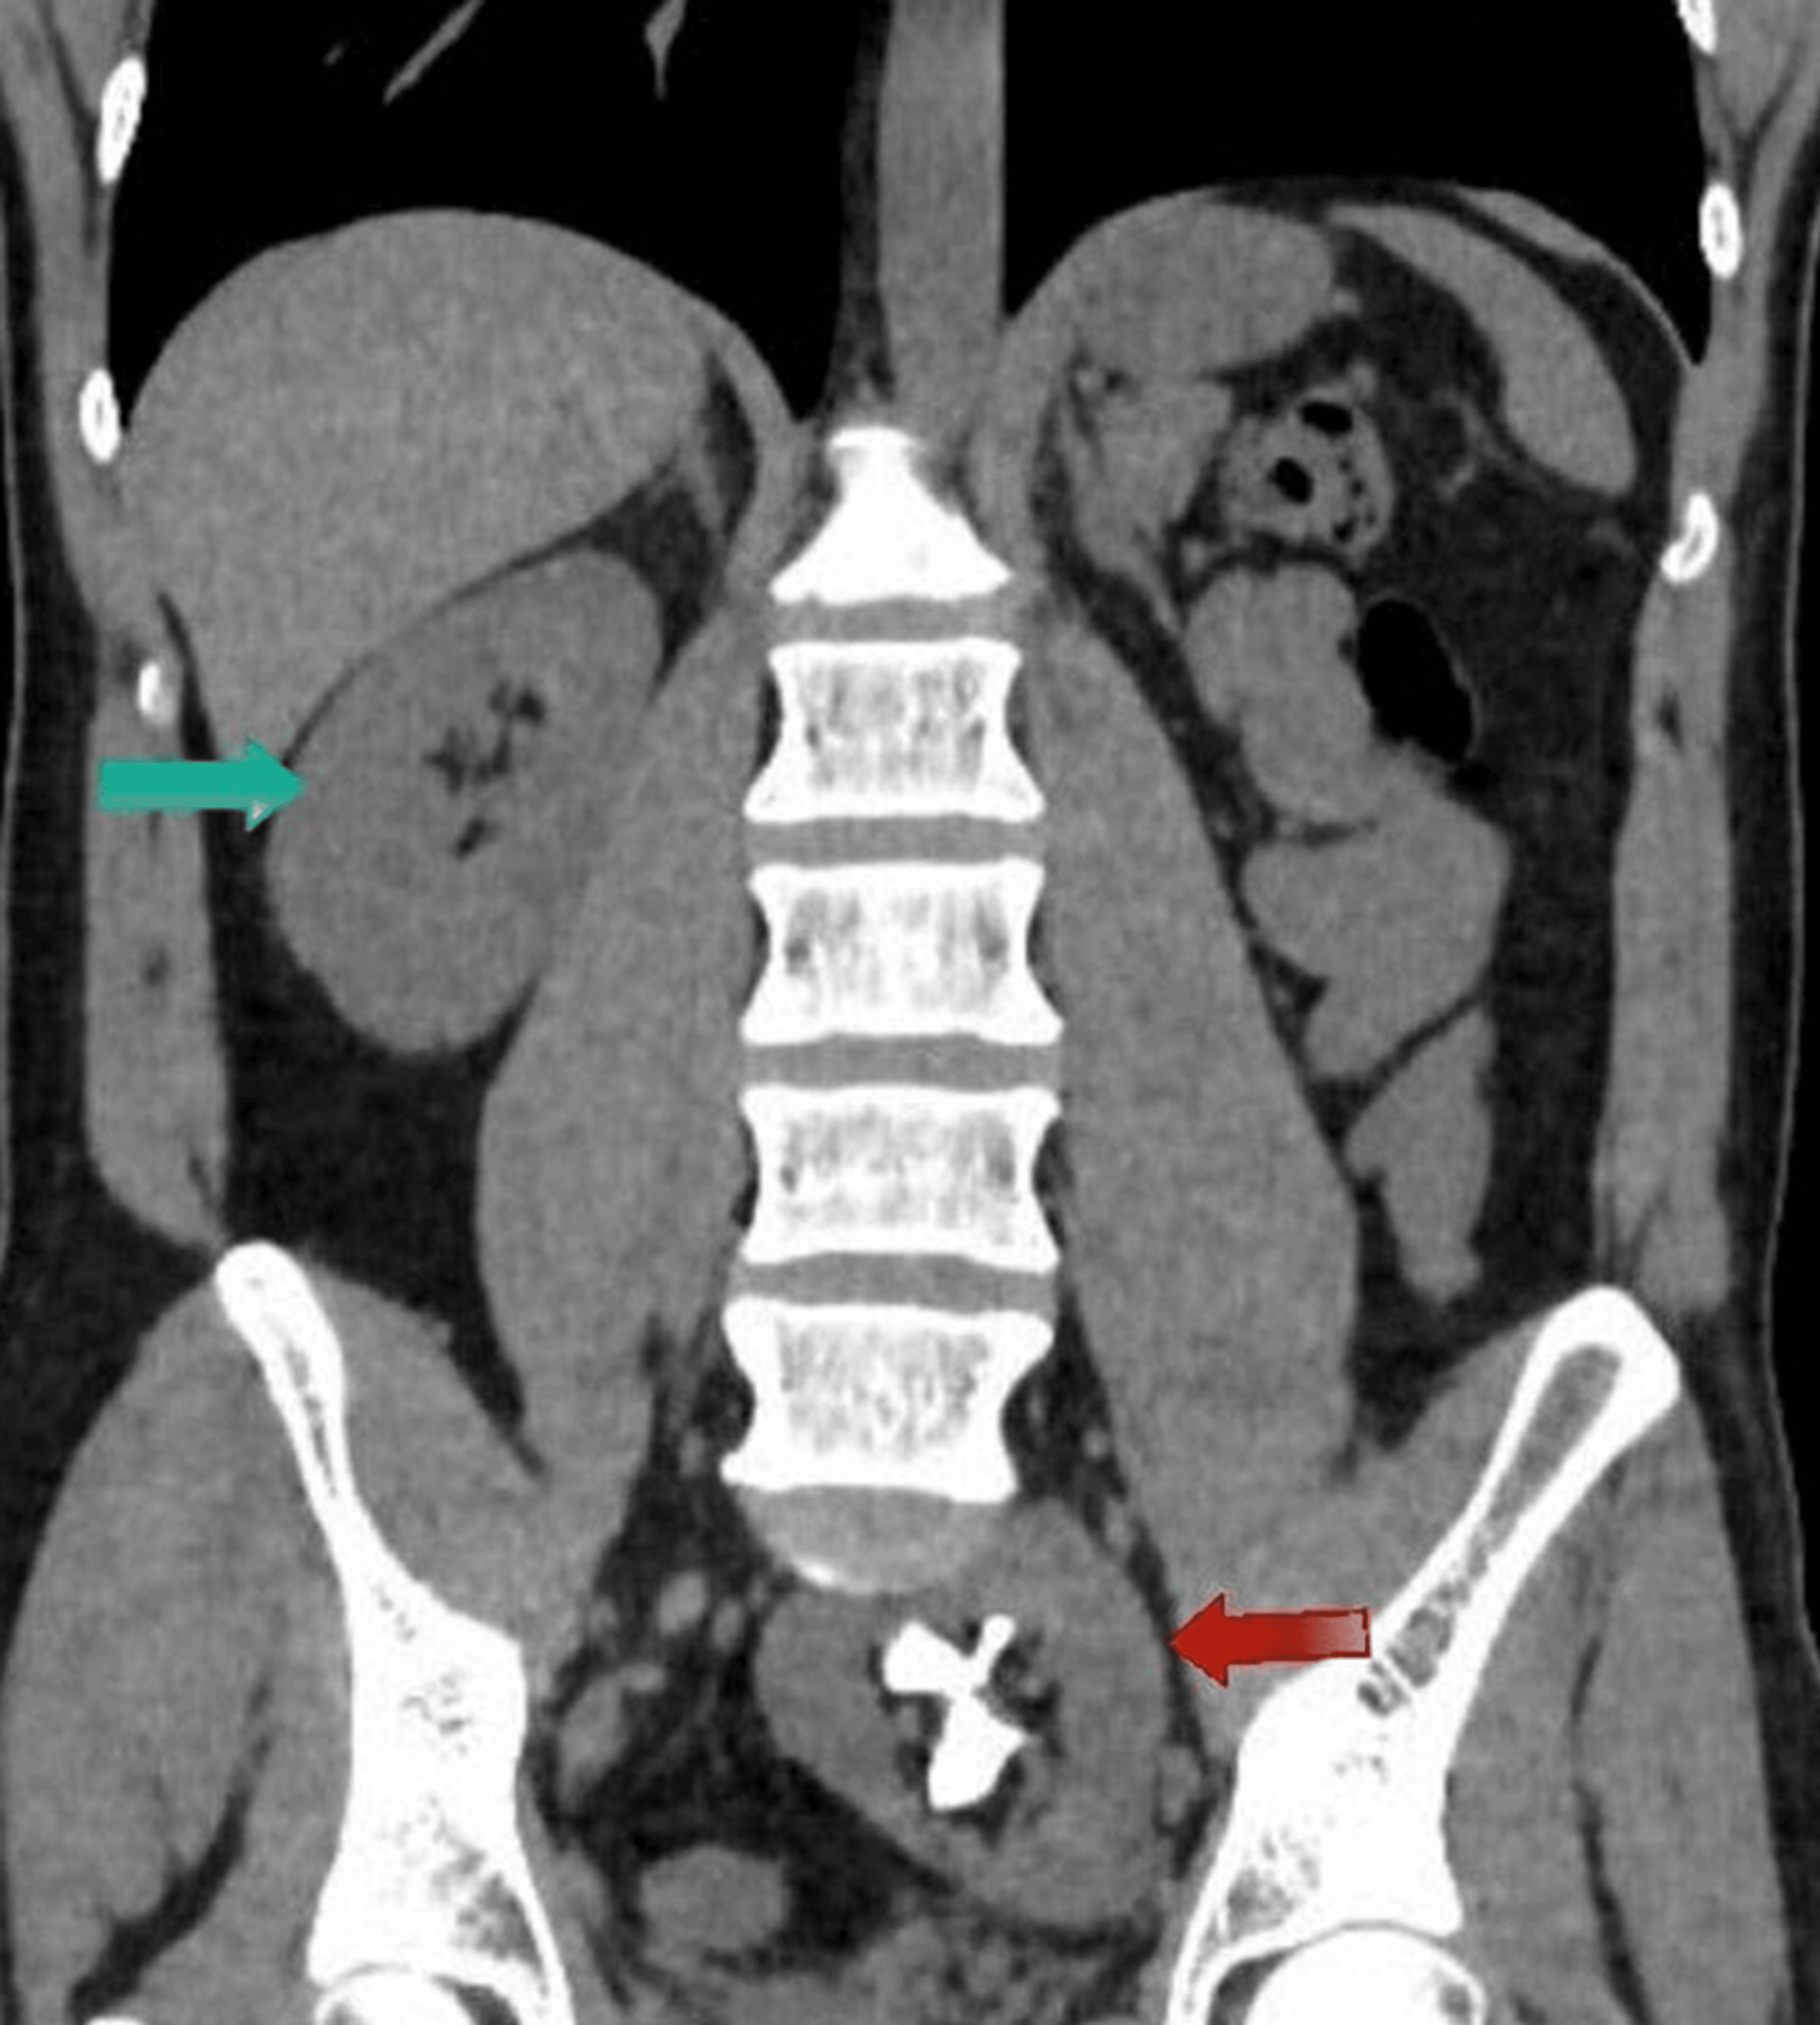

CT scan with coronal image of ectopic left pelvic kidney showing the Ectopic Fused Pelvic Kidney Radiology If the kidney does not enter the retroperitoneal fossa, it is termed ectopic, and if it remains within the pelvis, it is deemed a pelvic kidney. Four types of crossed renal ectopia (fig 14) can be seen at imaging, mainly at ct and mri, including cre with fusion characterized by the ectopic kidney crossing over to the opposite side, with. Ectopic Fused Pelvic Kidney Radiology.

A computed tomography (CT) scan revealed an ectopic pelvic left kidney Ectopic Fused Pelvic Kidney Radiology An emergency ultrasound scan of the abdomen was reported as non. Crossed fused renal ectopia is then further divided depending on the orientation and position of the fused kidney. Four types of crossed renal ectopia (fig 14) can be seen at imaging, mainly at ct and mri, including cre with fusion characterized by the ectopic kidney crossing over to the. Ectopic Fused Pelvic Kidney Radiology.